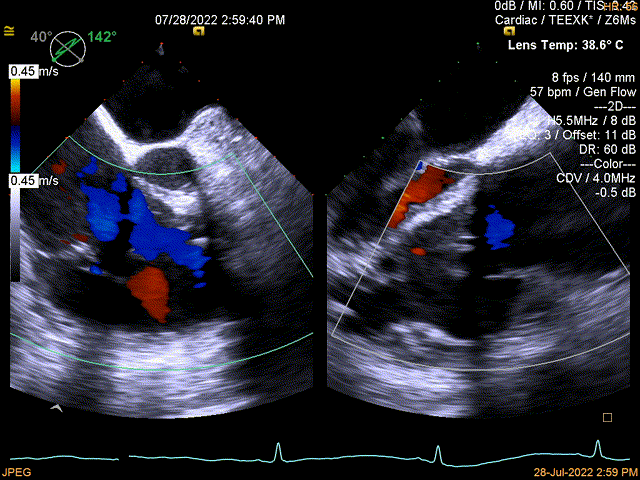

图1:术前TEE

术前TEE提示三尖瓣瓣叶活动尚可,无明显脱垂,隔瓣较短,反流束来源于后瓣及隔瓣交界处,后瓣及隔瓣对合缘保留良好,反流束同时向前隔交接延伸。